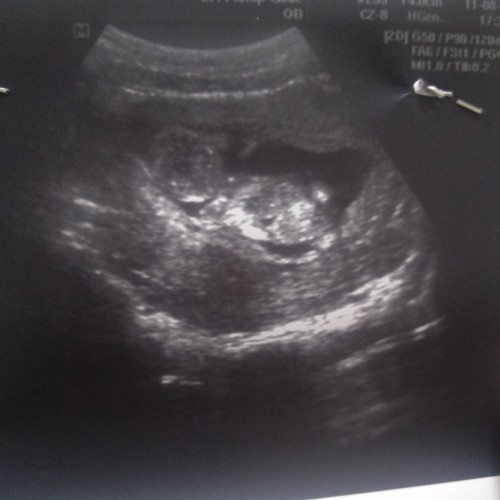

แม่แม่คะช่วยดูภาพหน่อยนะคะ

อยากรู้ว่าส่วนใหญคืออะไรบ้างแล้วน้องนอนท่าใหนคะ ขอบคุณค่ะ#ขอบคุณล่วงหน้านะคะ #ใครมีประสบการณ์

นอนคว่ำ หันหัวไปทางซ้ายค่ะ

น้องนอนคว่ำหน้าค่ะ

น่าจะนอนคว่ำค่ะ

นอนคว่ำหน้าค่ะ

นอนคว่ำคะ